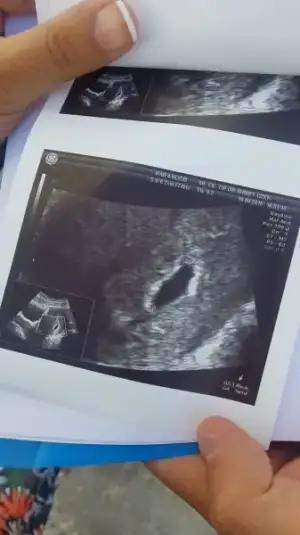

kese görünümünüz nasıl. benim ilk 4 haftalıkken yusyuvarlaktı 5.hafta da ince uzun şekle girmişti. doktor bişi demedi sağlıklı gebelik dedi kan pıhtıları filan yok dedi. kese rahim de oluşmuş dedi. dış gebelik vs değil dedi. kalp atışı için haftaya gelin dedi ama yine de internetten baktığımda herkesin kesesi yuvarlak.

Benimkide böyleydi. Sizin bu resimde ne kadarlıksınız. Birde kese boyu kaç mm

bu kese 19 eylül tarihine ait. yani 5 gün önce. 1.05 cm. doktorun deyimi ile 10.5 mm. 18 eylül tarihli kan değerim de 6884.97

Benim 17 eylülde 6+1. Boyu 14 mm di. Haftasıyla uyumlu dedi. Beta ya bakmadı. Tahminimce 7000 lerdeydi benimde.